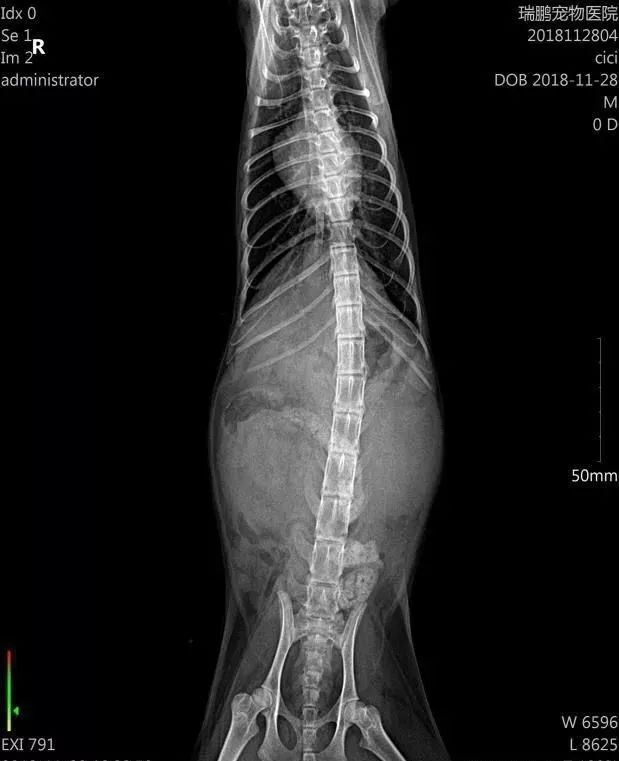

在11月25号我带它去宠物医院,拍片—抽血。

于是我转战到另外一个宠物医院,医生接手了,于是又一次化验-做B超及其他检验,隔天才有结果,等到第二天,医生告诉我是“肾脏大”